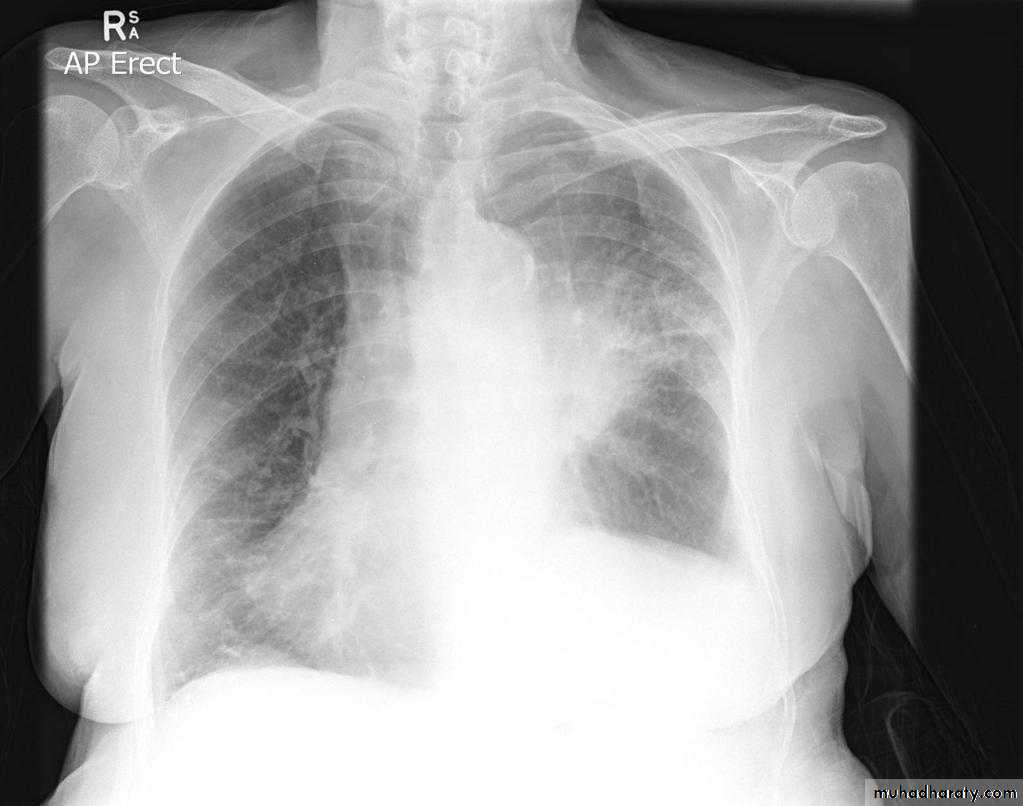

70.Bronchogenic CA

2 Radioopaque lesions can be seen in the right lung one is hilar(central) and the other is periphral both of them have speculated margins( sun ray appearance)

radioopaque mass with speculated margine can be seen in the upper zone right lung